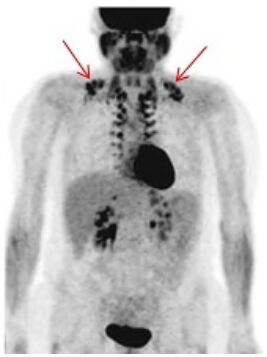

26.病人接受,出現圖中紅色箭頭標註之生理性攝取現象,下列敘述何者錯誤?

(A)可能會降低該區域腫瘤偵測的準確度 (B)常見於寒冷天氣和年輕、瘦弱的患者 (C)使用鎮靜劑可能造成此類現象較容易發生 (D)為減少此現象,可在注射前給患者保持溫暖 30~60 分鐘